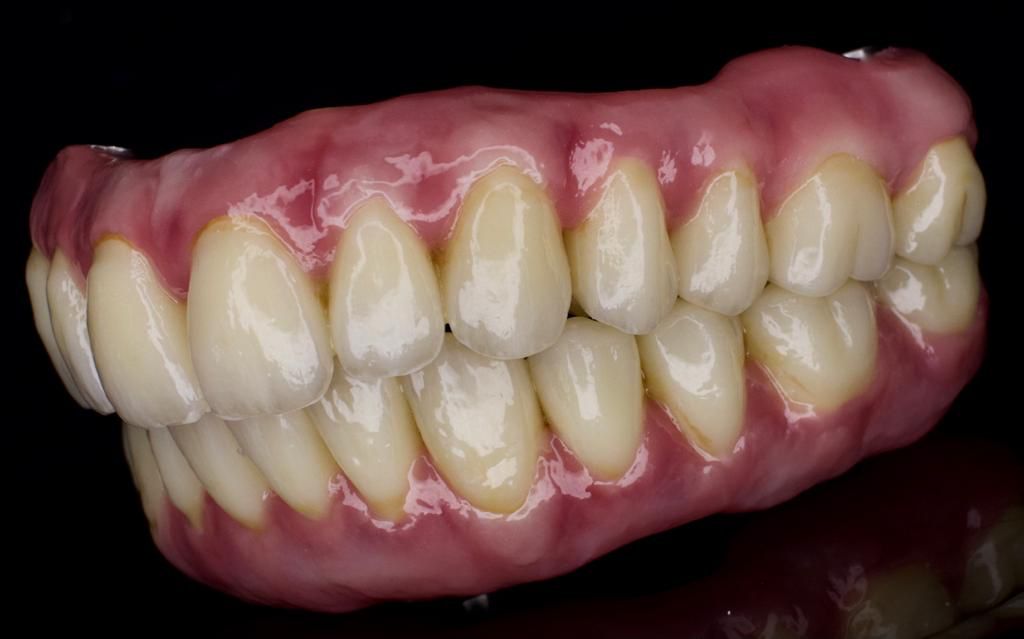

After a healing period of 12 weeks, we then started the design process of making his permanent teeth. After designing it, we did some try ins which the patient is over the moon, and now he has a fixed bridge at the top and a fixed bridge at the bottom.

He is over the moon with his new smile, and can’t wait to spend time with his grandkids and not having to worry about his teeth.